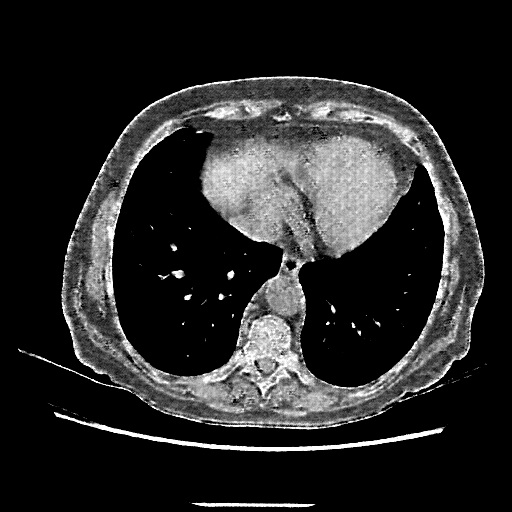

Generated VENOUS CT scan (A→B translation)

Full window (WL 1023.5, WW 4095 β†’ Low βˆ’1024, High +3071)

Lung window (WL -600, WW 1500 β†’ Low βˆ’1350, High +150)

Mediastinum window (WL 40, WW 400 β†’ Low βˆ’160, High +240)